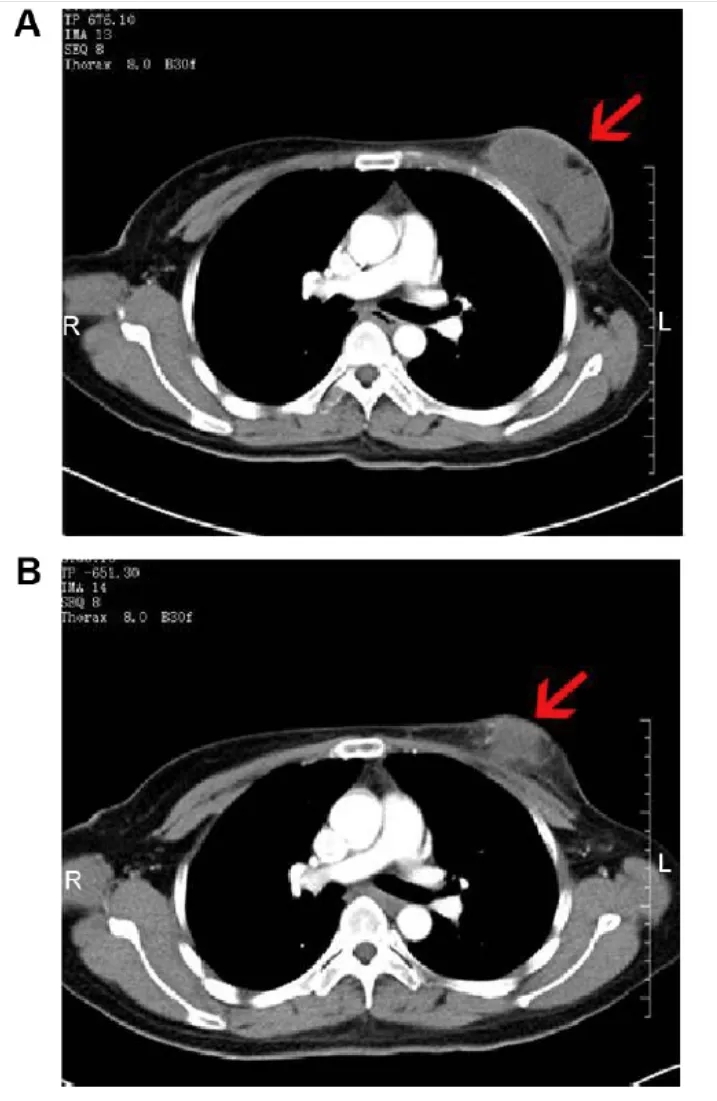

该患者治疗前后的影像学变化尤为典型:治疗前CT扫描显示,其右乳存在8.0×3.8×5.7cm的软组织肿块,边界模糊,增强CT呈中度不均匀强化;腋窝可见多处肿大淋巴结,最大者约2.9×1.7×3.8cm(详见下图A)。经NK细胞治疗2个月后,影像学复查显示肿块缩小至6.8×3.5×5.8cm,强化程度减弱为轻度不均匀;腋窝肿大淋巴结亦显著缩小(详见下图B),展现出NK细胞疗法在复发性乳腺癌中的潜在抗肿瘤活性。

▲图源“Dovepress”,版权归原作者所有,如无意中侵犯了知识产权,请联系我们删除